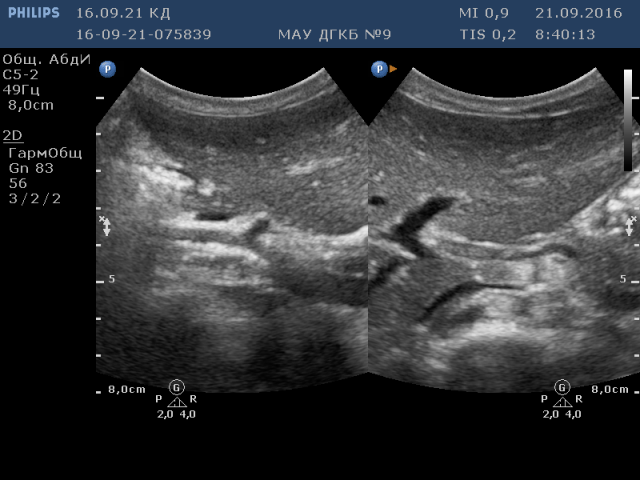

На левом фото (сагиттальная плоскость) чётко видно отхождение ЧС от ВБА

А на правом фото представлены только ветви чревного ствола (треножник Галлера).

1. ВБА

2. ЧС

3. АО

Все как всегда, очень часто ВБА и ЧС отходят от АО рядышком, практически вплотную!!!